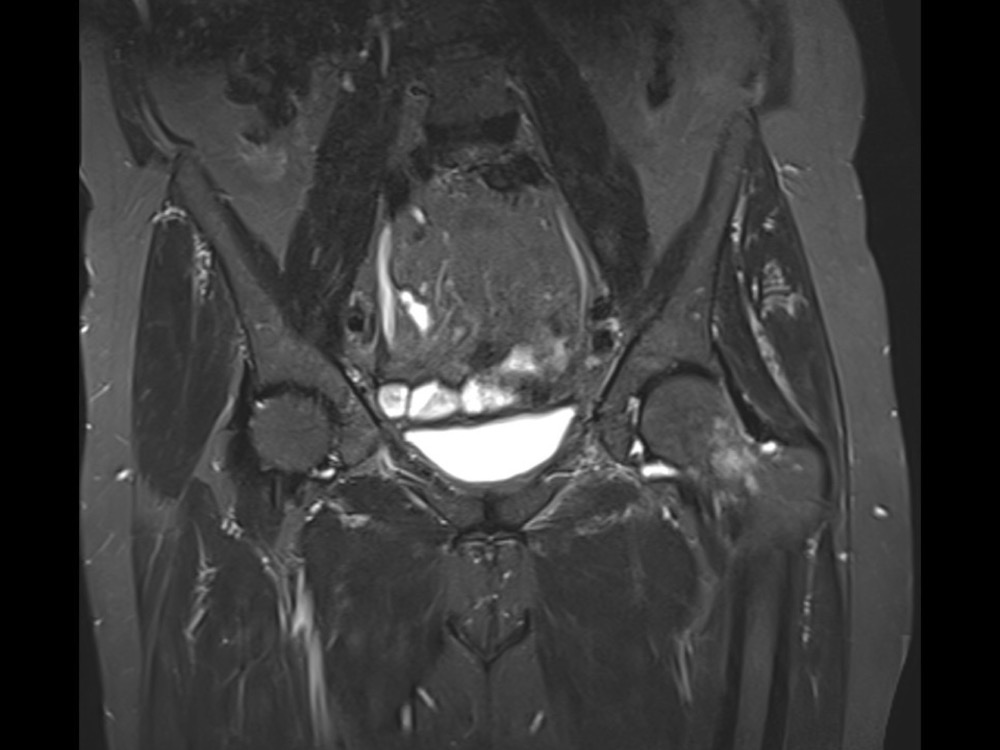

Douleurs de hanche

Linda Ouerd 06/11/2019